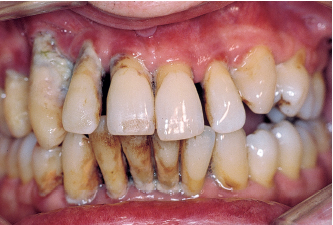

Fig 1-2a Aggressive periodontitis in a 50-year-old man. There is significant functional impairment; all teeth are mobile.

Fig 1-2b Destruction and attachment losses exceed 9 mm.